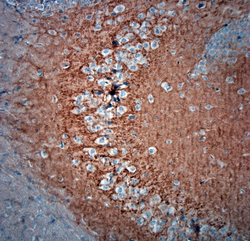

- Experimental details

- 4HC-P on paraffin sections of mouse brain. The animal was perfused using Autoperfuser at a pressure of 130 mmHg with 300 ml 4% FA before being processed for paraffin embedding. HIER: Tris-EDTA, pH 9 for 20 min using Thermo PT Module. Blocking: 0.2% LFDM in TBST filtered thru 0.2 um. Detection was done using Novolink HRP polymer from Leica following manufacturer's instructions; DAB chromogen. Primary antibody dilution 1: 1000, incubated 30 min at RT using Autostainer. Sections were counterstained with Harris Hematoxylin. Small neurons are stained and also some nuclear staining is observed.